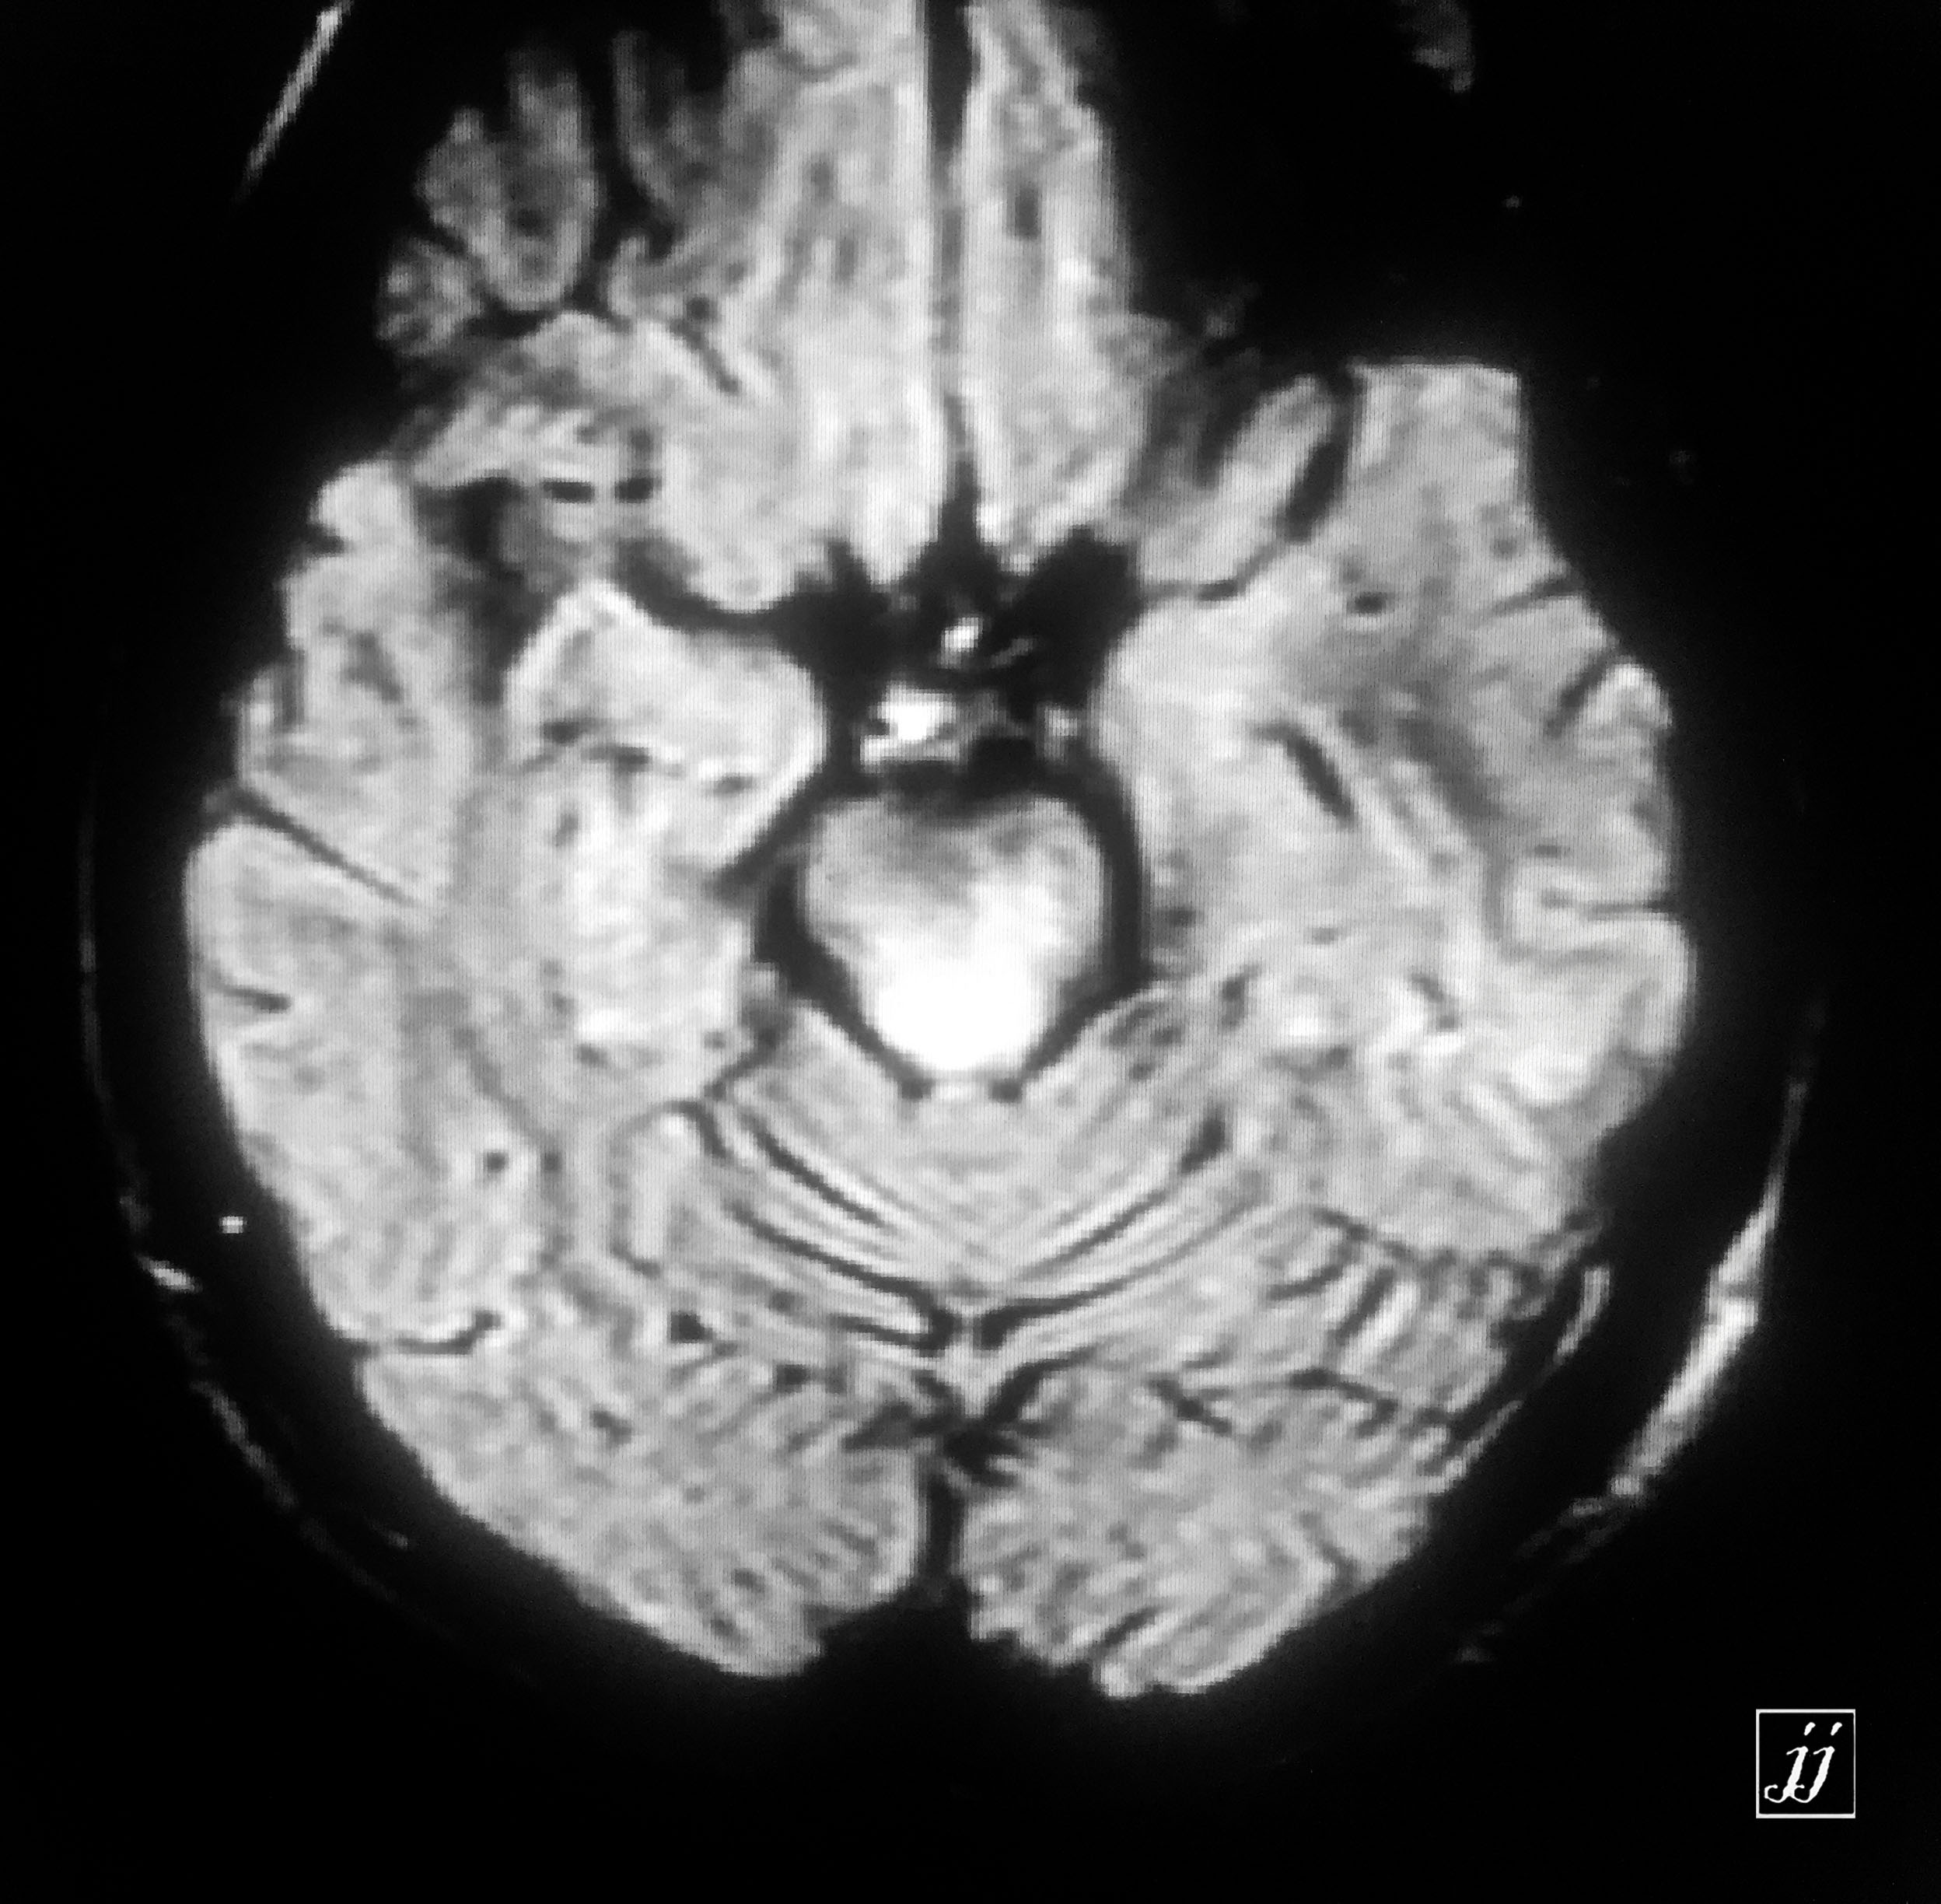

Brain- deep white mater abnormal signal degenerative type (1)